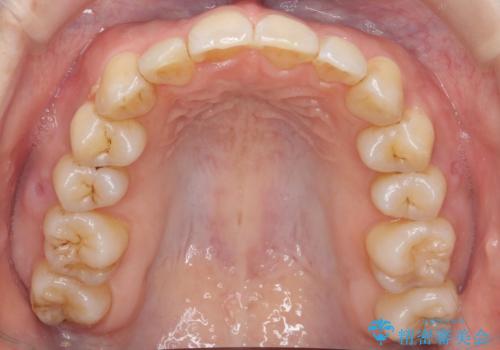

やや難ケース 上の歯を抜かずに歯列を後ろに下げて治療 4本ではなく下1本のみの抜歯できれいに

- 前歯のがたつき 歯並びを主訴に来院。

右の上下の混雑が激しく、通常は上下左右4本抜歯も相当する症状でした。

前歯の角度もよくなり、奥歯のかみ合わせも問題なく、上は非抜歯で口元も閉じやすくなりました。